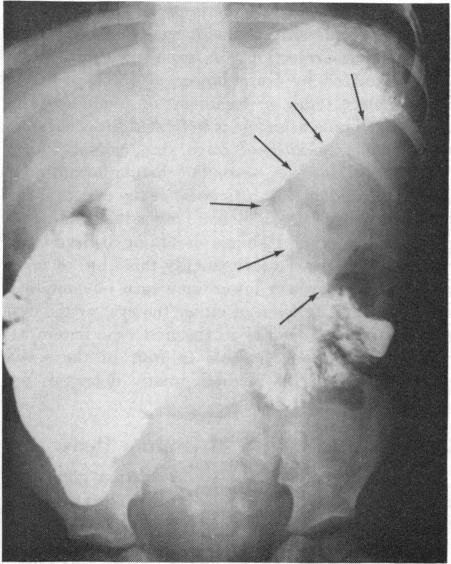

Surgeons whose practice involves many infants and children should be acquainted with all abnormalities of pancreatic malformation and function. Conditions amenable to surgical treatment are few, but serious. Trauma to the pancreas in childhood is most commonly diagnosed by fever, leukocytosis, rectus spasm and elevated serum amylase. Drainage of the lesser sac and debridement of devitalized tissue may prevent the sequelae of pseudocyst formation which seems to follow the untreated injury. True congenital cysts are characterized by an epithelial lining.Mucoviscidosis complicated by meconium ileus remains a challenging disease of the newborn that requires early operation. Ten per cent of infants with cystic fibrosis may be threatened by intestinal obstruction from this cause. Some children surviving the newborn period go on to develop obstruction later. Annular malformation of pancreas may produce upper intestinal (duodenal) obstructive symptoms immediately after birth. Surgical correction by duodenojejunostomy should be postponed only long enough to correct severe fluid or electrolyte imbalances. Idiopathic spontaneous hypoglycemia has the most serious prognosis if convulsions are allowed to recur. Increased metabolic rates in infants increase the need for control of blood sugar levels by either administration of cortisone or pancreatic resection. If adenoma is the cause, a conservative resection of the tumor suffices. If serial frozen section fails to reveal either tumor or hypertophy of insulin-producing cells, blind pancreatectomy may be indicated, for irreversible brain damage develops early in uncontrolled hypoglycemia.